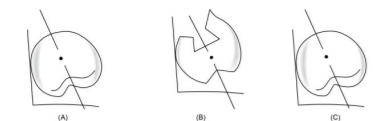

Meyer’s classification for knife edge ridges:

⛔Saw-tooth

⛔Razor-like

⛔Ridge with discrete spiny projections